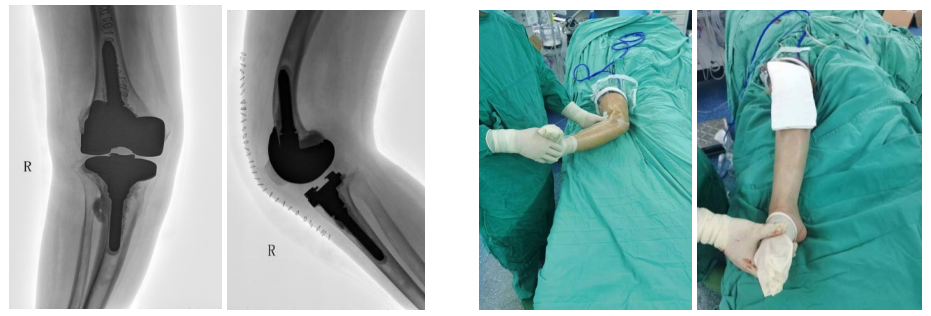

2022年02月22日,左镇华主任医师带领骨科团队在麻醉科及手术室的配合下为患者行左全膝关节置换术+股骨远端截骨钢板内固定术,手术顺利。术后第一天,患者即在医生及康复师的指导下行左股四头肌、关节被动及主动功能锻炼。术后10天左右转入我院康复医学科行功能锻炼,拆线后出院。

第一次术前及术后X片影像 第一次术后体位照